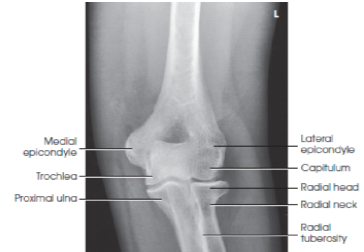

Structures shown/evaluation criteria for AP elbow

• think ulna

-joint space

-epicondyles

-fossae

A

radial head, neck, and tuberosity slightly superimposed over the proximal ulna

elbow joint open and centered to CR

no rotation of humeral epicondyles

coronoid and olecranon fossae approximately equidistant to epicondyles